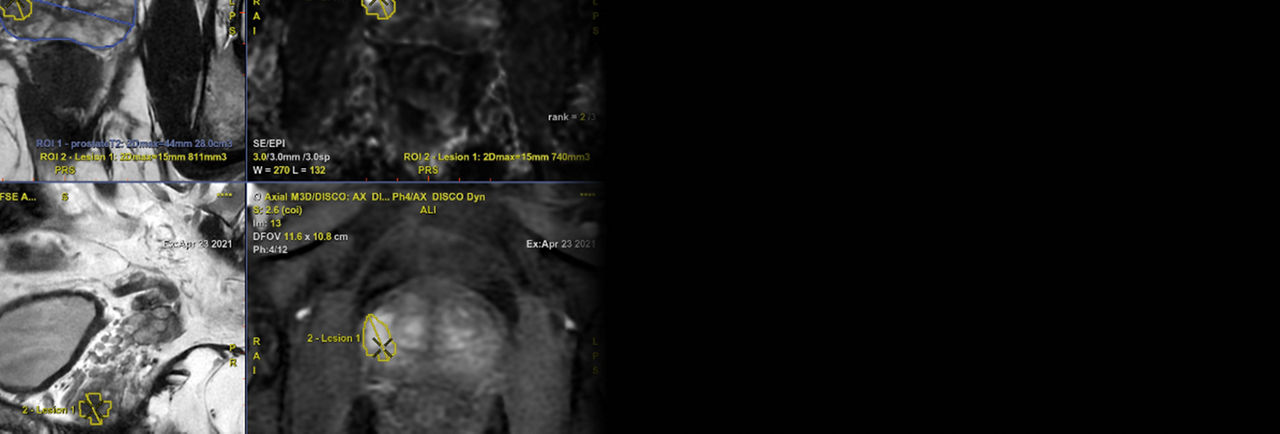

It is designed to work with icobrain⁶ and PROView to help support decision making in neuro and prostate imaging. SIGNA One is a streamlined accessible platform designed to fuel your research ambitions and transform possibilities into realities.

From scan to report: SIGNA One works with icobrain and PROView to help support decision making in neuro and prostate imaging.